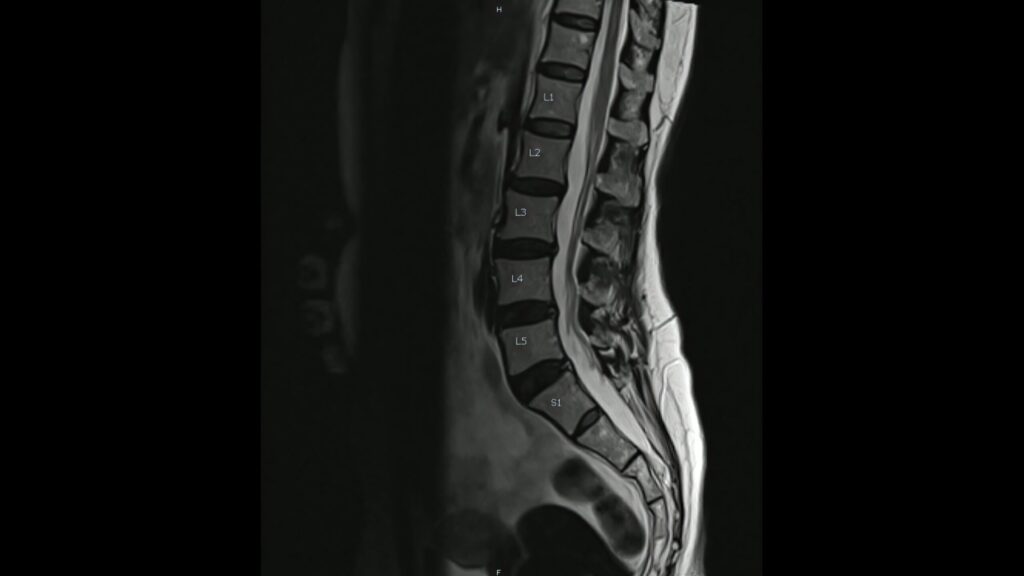

私たち人間が二足歩行という、生物学的には極めて不安定かつ野心的な移動様式を手に入れたその中心には、常に「脊椎」という名の精密な支柱が存在していました。この一本の柱は、単に頭部を支えるための棒ではなく、重力という絶え間ない物理的ストレスを分散し、中枢神経という最も重要なインフラを保護し、さらには四肢の自由な動きを可能にするための動的な「トラス構造」として機能しています。解剖学的な視点からその構造を紐解けば、頚椎から尾骨に至るまで、まるで緻密に計算された建築物のように椎骨が積み重なっていることがわかりますが、その真の凄みは個々の骨の形状ではなく、それらが織りなす「曲線」と「連動性」にこそ宿っています。脊椎を横から眺めた際に描かれる美しいS字状の生理的湾曲は、物理学的な観点から見れば、直立姿勢における衝撃吸収効率を最大化するための究極のデザインと言えるでしょう。

実際に工学的なモデルで計算すると、脊椎の強度はこの湾曲が存在することで、直線的な柱である場合と比較して数倍にまで高まることが示されています。フランスのバイオメカニクス研究者であるカパンジーが提唱した「脊椎の抵抗力は湾曲の数の二乗プラス一に比例する」という公式に基づけば、三つの湾曲を持つ私たちの脊椎は、直線の柱よりも十倍もの負荷に耐えうる計算になります。しかし、この完璧な設計も、現代社会という特殊な環境下では新たな課題に直面しています。

また、脊椎運動の真髄は「運動連鎖」という調和にあります。例えば、私たちが床にある荷物を拾い上げようと前屈する際、その動きは腰だけで完結しているわけではありません。足首の背屈から膝の制御、そして股関節の回旋を経て、ようやく脊椎の一つ一つの椎節がわずかに動くことで、大きな弧を描くことができます。もし、股関節の柔軟性が失われていたり、ハムストリングスが緊張して骨盤の後傾が妨げられていたりすれば、そのしわ寄せは全て腰椎へと集中します。腰椎は構造的に回旋や過度な屈曲に適した部位ではなく、本来は安定を司るべき場所です。そこに動的な負荷が集中することで、椎間板の髄核が線維輪を突き破る、いわゆる椎間板ヘルニアのリスクが急上昇するのです。私たちは、痛みが出た場所を「原因」と考えがちですが、脊椎のメカニクスにおいては、痛みは「結果」であり、真の原因は運動連鎖のどこかに潜む「動かない部位」の代償である場合が少なくありません。

さらに、脊椎の状態は私たちの精神や自律神経系とも密接にリンクしています。脊髄から枝分かれする神経根は、椎間孔という狭い隙間を通って全身へと伸びていますが、アライメントの崩れや筋の過緊張は、これらの神経伝達に微細なノイズを混入させます。胸郭が閉じた円背姿勢は、横隔膜の動きを制限して呼吸を浅くし、交感神経を優位にさせ、慢性的な疲労感やストレス感受性の増大を招くことが示唆されています。姿勢を正すという行為が、単なるマナーや見栄えの問題ではなく、自己調節機能を最適化するための「神経学的介入」であるとされる所以はここにあります。これからの時代、脊椎の健康を守るためには、日常の中での「中立(ニュートラル)」への回帰が鍵となります。それは、耳の穴、肩の峰、股関節の大転子、膝、くるぶしが一直線上に並ぶ、重力が最も味方をしてくれるポジションを見つける旅でもあります。私たちは一日の大半を椅子に座って過ごしますが、このとき骨盤の坐骨結節で正しく体重を受け、脊椎のS字を維持することは、椎間板への内圧を劇的に減少させます。デスクワークの合間に胸椎を伸展させ、縮こまった大胸筋を解放し、失われた頚椎のカーブを意識的に取り戻すリセット作業は、まさに脊椎という精密機械のメンテナンスに他なりません。